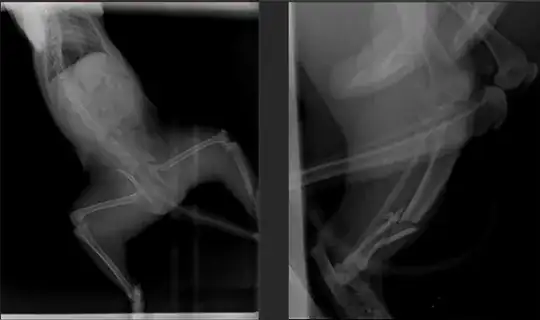

My 11-month-old cat has a broken pelvis and tibia in her back paw (see photo). According to the information I received, the pelvic bone may heal on its own, but the leg bone will most likely require surgery. This means two operations will be necessary: one to fix it with an iron and another to remove the iron after healing. I am concerned about having to put my cat through two surgeries. It has been 7 days since the fracture, and he refrains from moving his leg due to the pain. He tries to find a comfortable position on his own while lying down in the cage or getting up to avoid pain. He is more active with his other leg and handles the injured leg with great care. Please, by looking at the photo, could you advise me on whether the operation is necessary? Is there a chance the bone will heal well without surgery and my cat won't be lame?

I reviewed the answers provided in the related post, but I couldn't find an exact match for the injury my cat has. As my cat's condition differs from the cases mentioned, I want to highlight the importance of an evaluation based on the X-ray picture I uploaded. The X-ray will provide crucial information to determine whether my cat might avoid surgery or if it's necessary due to the fragmented bone injury. Your insights based on the specific X-ray are highly valued. Thank you.